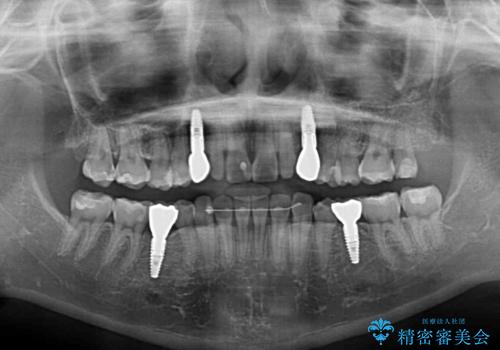

欠損と残存乳歯 矯正治療とインプラント治療

乳歯を残した状態は予後がよくないこと、矯正治療と補綴治療を総合的に進めていきたいとのことで、インビザラインによる矯正治療とインプラント補綴治療を並行して進めていくこととしました。

当院は矯正治療もインプラント補綴治療も、同一の歯科医師が担当するため、矯正治療を行いながら、最適なタイミングでインプラント補綴治療を行うことが可能です。

気になっていた部分がすべて解消され、患者様には大変満足していただきました。